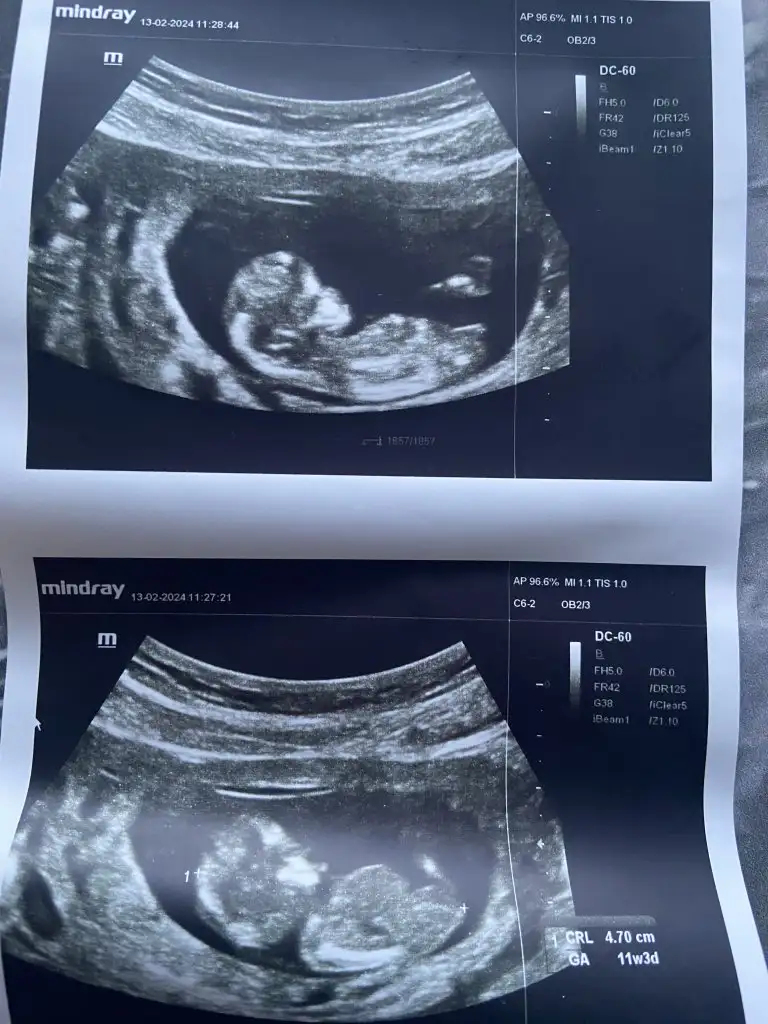

Sizin kız gibiEki Görüntüle 3373772 banada bakarmisiniz birinde 12 birinde 14 haftalık Eki Görüntüle 3373773

Sonda cikintimi var tam belli olmuyor orasiEki Görüntüle 3373772 banada bakarmisiniz birinde 12 birinde 14 haftalık Eki Görüntüle 3373773